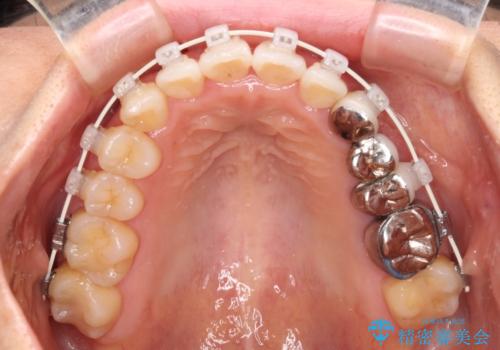

- 審美装置

- 上下前歯のデコボコと銀歯のブリッジを気にして来院された患者様です。

装着されているブリッジを切断して矯正治療を行うことや、手間をかけずに早めに治療を終えたいとのことで、目立たないワイヤー装置による矯正治療を行うこととしました。

矯正治療中に上下前歯が接触しない時期があり、咬み合わせ改善のために期間がかかるのではないかと懸念されましたが、結果的には補綴治療も含めて1年以内の短期間で終えることができました。